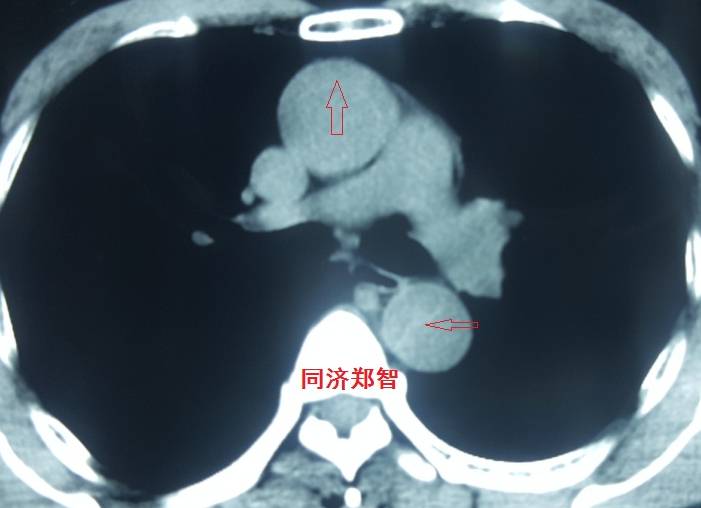

病例二

胸部平扫CT提示升主动脉增宽(红色星形标记),CTA证实A型主动脉夹层伴升主动脉夹层动脉瘤形成。